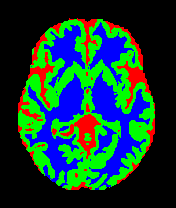

• MRBrainS13 [35]: From the MICCAI 2013 challenge, this dataset contains multi-sequence scans of 20 subjects acquired on a 3.0T Philips Achieva scanner. It provides T1 (TR: 7.97.9 ms, TE: 4.54.5 ms), T1-IR, and T2-FLAIR sequences. All scans are co-registered and bias-corrected with a voxel spacing of 0.96×0.96×3.000.96\times 0.96\times 3.00 mm. We utilize the provided labels for CSF, GM, and WM segmentation.

7 Qualitative Evaluation

Fig. 8 and Fig. 10 provide qualitative comparisons on the OASIS-1 and MRBrainS13 datasets, respectively. It is visually evident that the baseline predictions (c) and standard augmentations (e.g., (d), (g), (i)) frequently suffer from noisy artifacts, blurred boundaries, and mis-segmentation of intricate anatomical structures. In stark contrast, our ”Ours+” enhanced methods (e.g., (e), (h), (k)) consistently produce segmentation maps that are visibly cleaner, more spatially coherent, and demonstrate significantly sharper adherence to the Ground Truth (b). This superior fidelity is particularly noticeable in the complex sulcal patterns and holds true across all three backbones (rows), confirming that our framework yields more robust and anatomically plausible results.